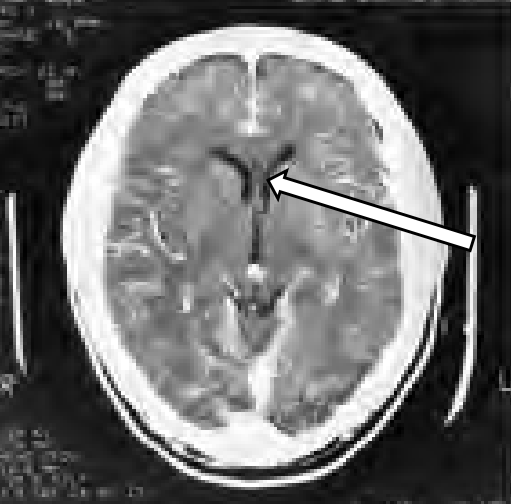

Strzałka na przedstawionym skanie TK wskazuje przestrzeń płynową o charakterystycznym kształcie litery „V” lub odwróconej „Y”, położoną symetrycznie w obrębie półkul mózgowych, tuż przy linii pośrodkowej. To jest typowy obraz komory bocznej – dokładniej jej rogów przednich (czołowych), widocznych w przekroju poprzecznym. W tomografii komputerowej komory wypełnione są płynem mózgowo–rdzeniowym, który w oknie mózgowym ma gęstość zbliżoną do wody i dlatego wygląda na ciemniejszy (hypodensyjny) niż tkanka mózgowa dookoła. W praktyce klinicznej umiejętność szybkiego rozpoznawania komór bocznych jest kluczowa: pozwala ocenić ich szerokość, symetrię, przemieszczenie oraz obecność zastoju płynu. Na podstawie kształtu i wymiarów komór bocznych radiolog ocenia np. wodogłowie, zanik mózgu, masy przemieszcające (guzy, krwiaki) czy skutki urazu. W standardowym opisie badania TK głowy zawsze odnosi się do układu komorowego – czy jest poszerzony, zapadnięty, czy zachowana jest linia pośrodkowa. Z mojego doświadczenia, w praktyce technika obrazowania bardzo pomaga kojarzenie topografii: komory boczne „siedzą” w obrębie półkul, komora III leży bardziej w środku, przy strukturach międzymózgowia, a wodociąg mózgu i komora IV schodzą w dół w kierunku pnia mózgu. Rozpoznanie komory bocznej na takim przekroju jest więc zgodne z klasycznym obrazem anatomicznym i dobrą praktyką opisu badań TK zgodnie z zasadami neuroradiologii.

Na tym obrazie TK głowy łatwo pomylić różne elementy układu komorowego, zwłaszcza gdy ogląda się pojedynczy przekrój, a nie całe badanie w sekwencji warstw. Wskazana przez strzałkę struktura ma jednak typowy wygląd i położenie dla przednich części komór bocznych, a nie dla pozostałych wymienionych odpowiedzi. Wodociąg mózgu (wodociąg Sylwiusza) jest wąskim kanałem łączącym komorę III z komorą IV. Leży w obrębie śródmózgowia, czyli znacznie bardziej ku tyłowi i ku dołowi, w rejonie pnia mózgu. W typowym przekroju osiowym TK głowy wodociąg, jeśli w ogóle jest widoczny, ma postać bardzo cienkiego, punktowego lub nitkowatego światła, a nie szerokiej, rozgałęziającej się przestrzeni w obrębie półkul. Pomyłka w tym kierunku zwykle wynika z traktowania całego układu komorowego jako jednej „dziury z płynem”, bez zwracania uwagi na topografię względem kory i sklepistości czaszki. Komora III ma z kolei kształt bardziej szczelinowaty, położona jest dokładnie w linii pośrodkowej, między wzgórzami, niżej niż rogi przednie komór bocznych. Na przekrojach, gdzie dobrze widać rogi przednie, komora III często nie jest jeszcze wyraźnie widoczna lub ma zupełnie inny, bardziej podłużny układ, a nie formę litery „V” w półkulach. Szyszynka natomiast jest strukturą miąższową, parenchymatyczną, a nie przestrzenią płynową. W TK często wykazuje drobne zwapnienia i wtedy wygląda jako jasny, niewielki punkt w okolicy tylnej części komory III, nad wzgórkami czworaczymi. Na prezentowanym obrazie strzałka nie wskazuje takiego punktowego, hiperdensyjnego ogniska, tylko symetryczną przestrzeń wypełnioną płynem. Typowym błędem jest tu ocenianie „kształtu” bez uwzględnienia kontekstu anatomicznego – gdzie jest sklepistość, gdzie są półkule, gdzie pień mózgu. Dobra praktyka w diagnostyce obrazowej zakłada zawsze korelację struktury z jej położeniem w trzech płaszczyznach i znajomość tego, które elementy układu komorowego powinny być widoczne na danym poziomie przekroju. Dzięki temu łatwiej uniknąć takich pomyłek i prawidłowo rozróżnić komory boczne, komorę III, wodociąg oraz drobne gruczoły jak szyszynka.